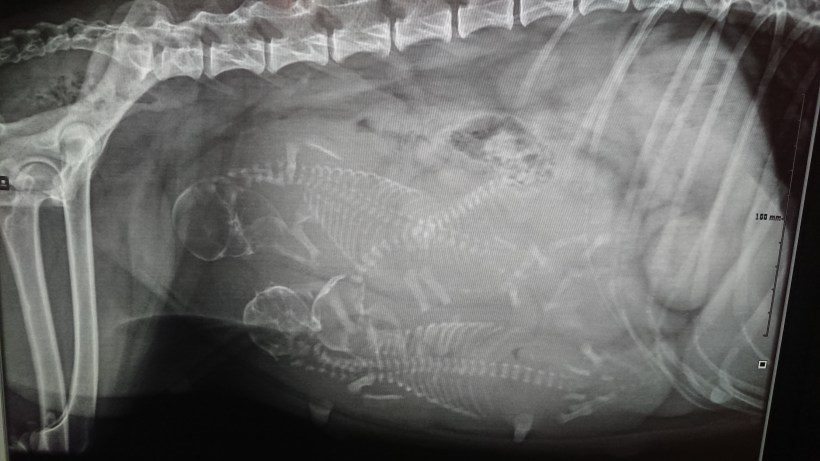

Röntgen genomförd!

Idag den 2/4 röntgades Mini och det gick att se tre valpar i magen. Nu glädjer jag mig att få se dem ute i verkligheten också. Blir spännande att se vad det är som kommer. Man känner nu tydligt att de rör på sig därinne. Än så länge har allt gått bra.